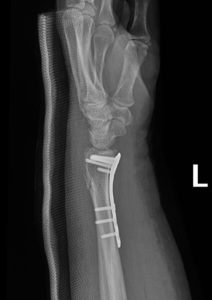

if the fracture is displaced, surgery may be needed to put the bone back into the correct position and fix the bone with Plates & screws or nails for adequate healing to occur.

- Wrist Fractures.